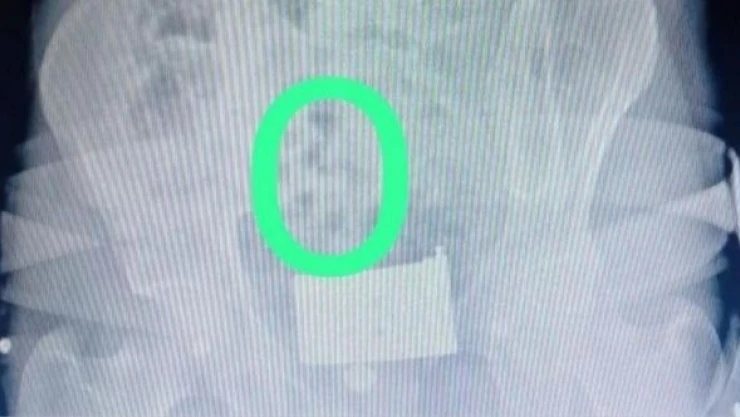

Araçtaki 2 yabancı uyruklu, şüpheli hareketleri üzerine iç beden muayenesi için hastaneye götürüldü. Muayene ve röntgeni çekilen İran uyruklu A.F. ve S.G'nin 558,83 gram eroni 64 kapsül haline getirerek yuttukları tespit edildi. Gözaltına alınan zanlılar, emniyetteki işlemlerinin ardından sevk edildikleri adliyede çıkarıldıkları sulh ceza hakimliğince tutuklandı.